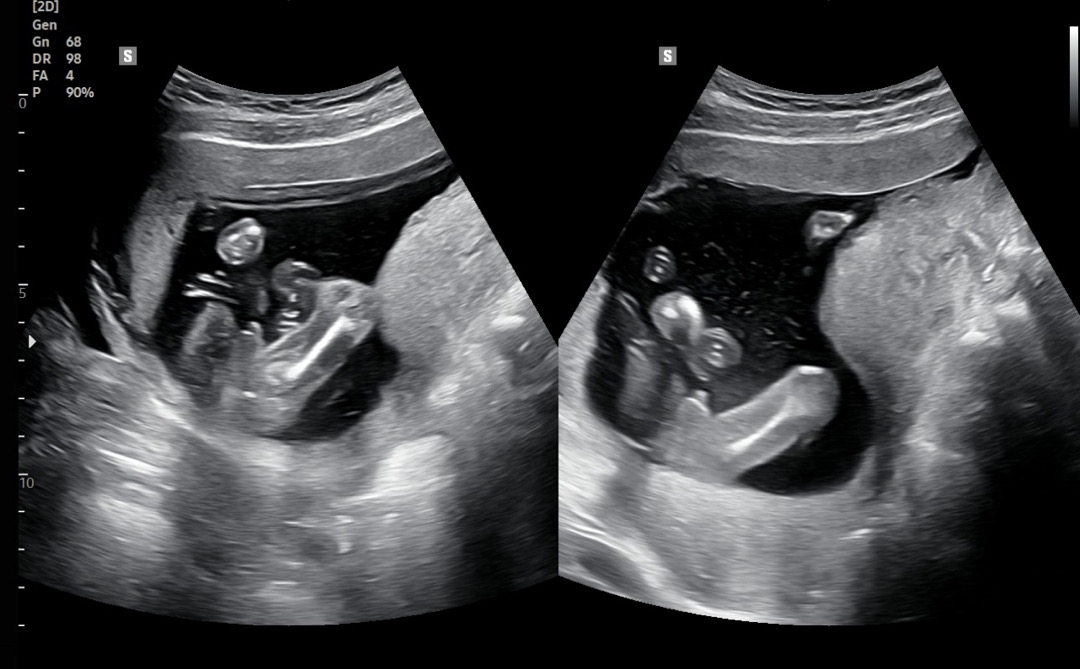

17주차 성별 봐주세요~!!!

원장님이 잘모르겠다는 식으로 말씀하셔서요...! 튀어나온게 고추일까요..탯줄일까요... 아들들은 더 뾰족하게 튀어나온 느낌이라ㅠㅠ! 성별이 뭘까요....?!

아들 100프로 ,,, 저랑똑같습네다 탯줄은 한줄로 길~고 뱀같이 다거슨 꽈츄

고츄네유!

아들같아여